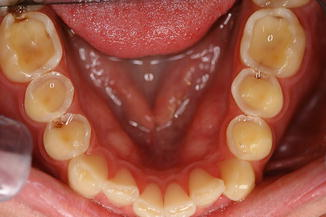

여러 음료에 치아를 4시간, 12시간 노출시켰을 때 치아표면의 변화를 살펴 보겠습니다.

증류수(Distilled water)와 비교하였을 때 대부분의 음료들이 치아 표면을 침식 시킨 것이 관찰됩니다.

탄산수에 의해서 법랑질 표면이 손상된 사진을 보셨습니다.

이렇게 손상된 구조는 다시 돌아오지 않습니다.